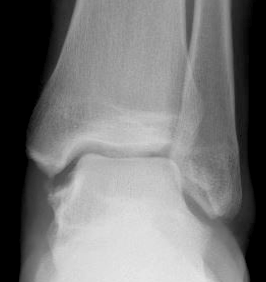

| Anterior drawer | Talar tilt |

|---|---|

| Assess ATLF | CFL test / subtalar instability |

|

10° plantarflexion neutral rotation Draw talus anterior to tibia |

10-20° plantarflexion Ankle inversion |

| > 3mm difference to other ankle | > 20o difference to other ankle |